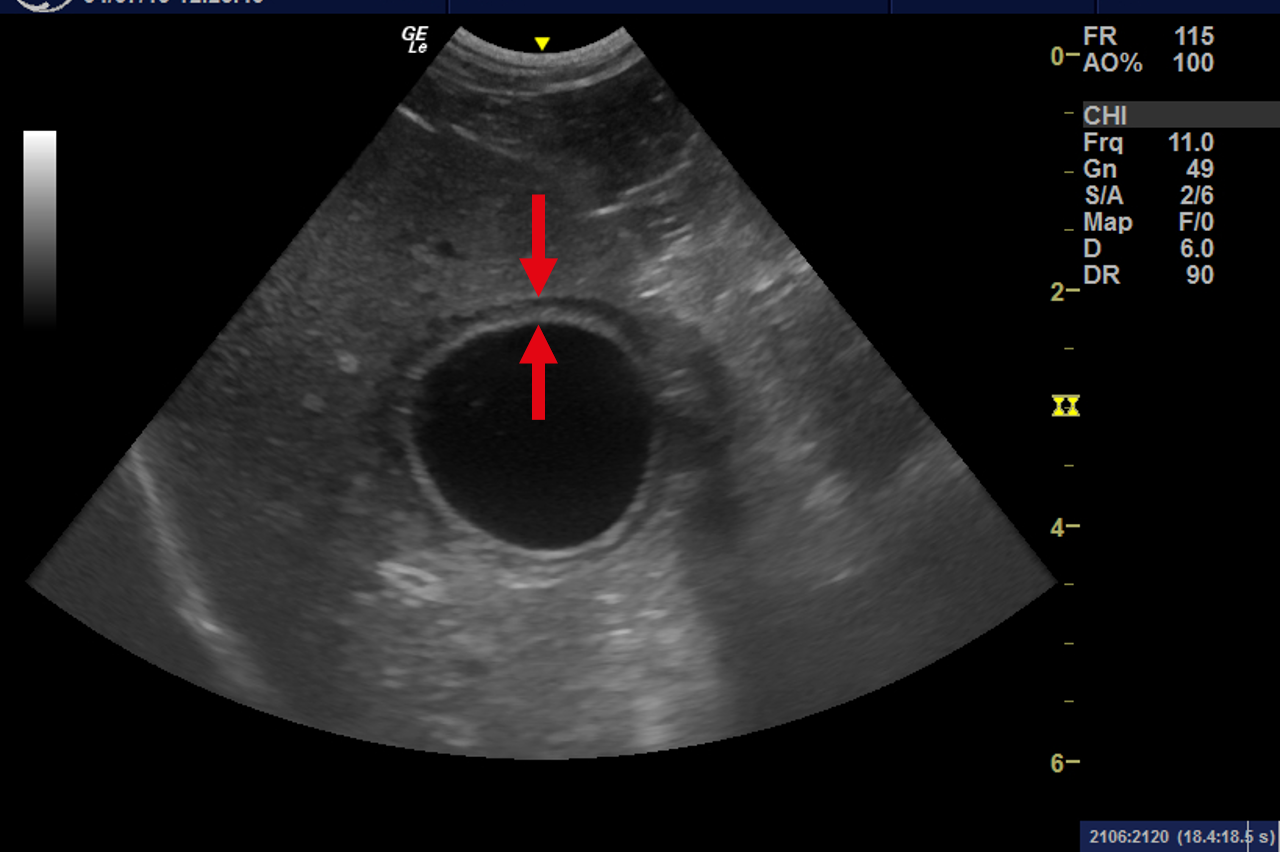

Ultrasonography of the Kidneys >>